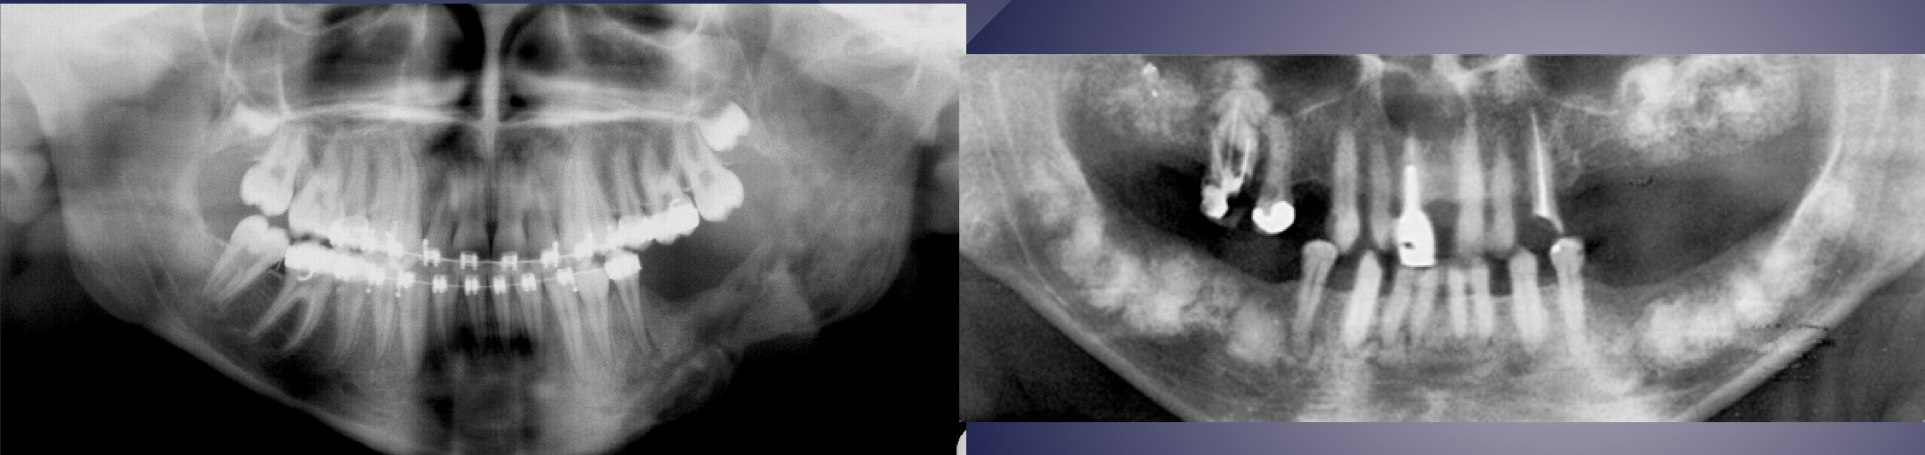

which is osteomyelitis?

L picture: osteomyelitis: ill-defined, mixed density lesions above and below IAN canal, moth eaten VS R: not osteomyelitis, well defined radiopaque lesions in maxilla and mandible above IAN canal